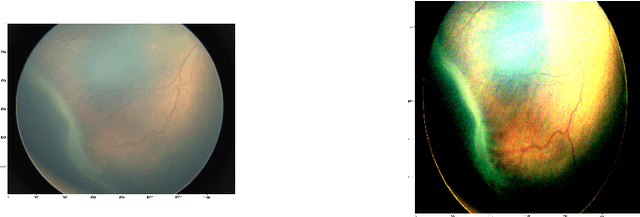

Abstract:Retinal vascular diseases affect the well-being of human body and sometimes provide vital signs of otherwise undetected bodily damage. Recently, deep learning techniques have been successfully applied for detection of diabetic retinopathy (DR). The main obstacle of applying deep learning techniques to detect most other retinal vascular diseases is the limited amount of data available. In this paper, we propose a transfer learning technique that aims to utilize the feature similarities for detecting retinal vascular diseases. We choose the well-studied DR detection as a source task and identify the early detection of retinopathy of prematurity (ROP) as the target task. Our experimental results demonstrate that our DR-pretrained approach dominates in all metrics the conventional ImageNet-pretrained transfer learning approach, currently adopted in medical image analysis. Moreover, our approach is more robust with respect to the stochasticity in the training process and with respect to reduced training samples. This study suggests the potential of our proposed transfer learning approach for a broad range of retinal vascular diseases or pathologies, where data is limited.

Abstract:Retinopathy of prematurity (ROP) is an abnormal blood vessel development in the retina of a prematurely-born infant or an infant with low birth weight. ROP is one of the leading causes for infant blindness globally. Early detection of ROP is critical to slow down and avert the progression to vision impairment caused by ROP. Yet there is limited awareness of ROP even among medical professionals. Consequently, dataset for ROP is limited if ever available, and is in general extremely imbalanced in terms of the ratio between negative images and positive ones. In this study, we formulate the problem of detecting ROP in retinal fundus images in an optimization framework, and apply state-of-art convolutional neural network techniques to solve this problem. Experimental results based on our models achieve 100 percent sensitivity, 96 percent specificity, 98 percent accuracy, and 96 percent precision. In addition, our study shows that as the network gets deeper, more significant features can be extracted for better understanding of ROP.